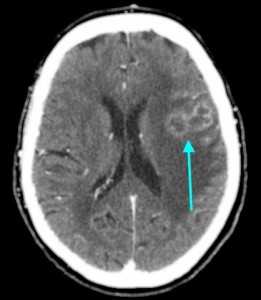

Метастазы головного мозга, фото. На КТ с контрастным усилением у пожилой пациентки (в верхнем ряду слева) с жалобами на головные боли выявлены множественные объемные образования в левом полушарии мозга, интенсивно накапливающие контрастное вещество. Образования имеют характерную форму в виде «кольца». На изображениях в нижнем ряду и вверху справа определяются множественные очаги в головном мозге: отчетливо видны округлые образования с более плотным «ободком» по периферии, располагающиеся в левой теменной доле.